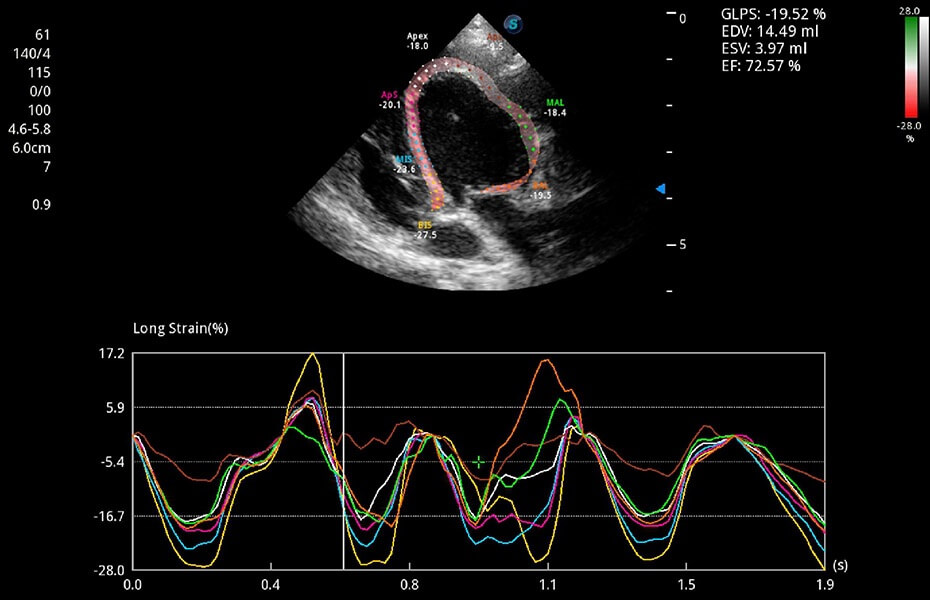

ProPet 60 作为一款高端台式动物超声设备,为动物医生的日常诊断提供了一系列贴合动物临床需求、解决临床实际问题的高级成像功能。凭借全系列高清探头,满足医生对腹部、心脏、生殖、浅表、肌骨等成像的所有需求,切实帮助您提升检查效率,提高诊断信心。

动物是人类最亲密的朋友和最值得信赖的伙伴。开立医疗也一直致力于探索动物专用的超声影像解决方案。 全新推出的ProPet系列,是开立在动物超声影像智能化、专业化、精准化的一次跨越式革新。动物不能用言语来表述自己的不适,通过超声影像,ProPet系列搭建了动物医生与不同物种沟通的“桥梁”,为动物医生注入了“治愈之力”。